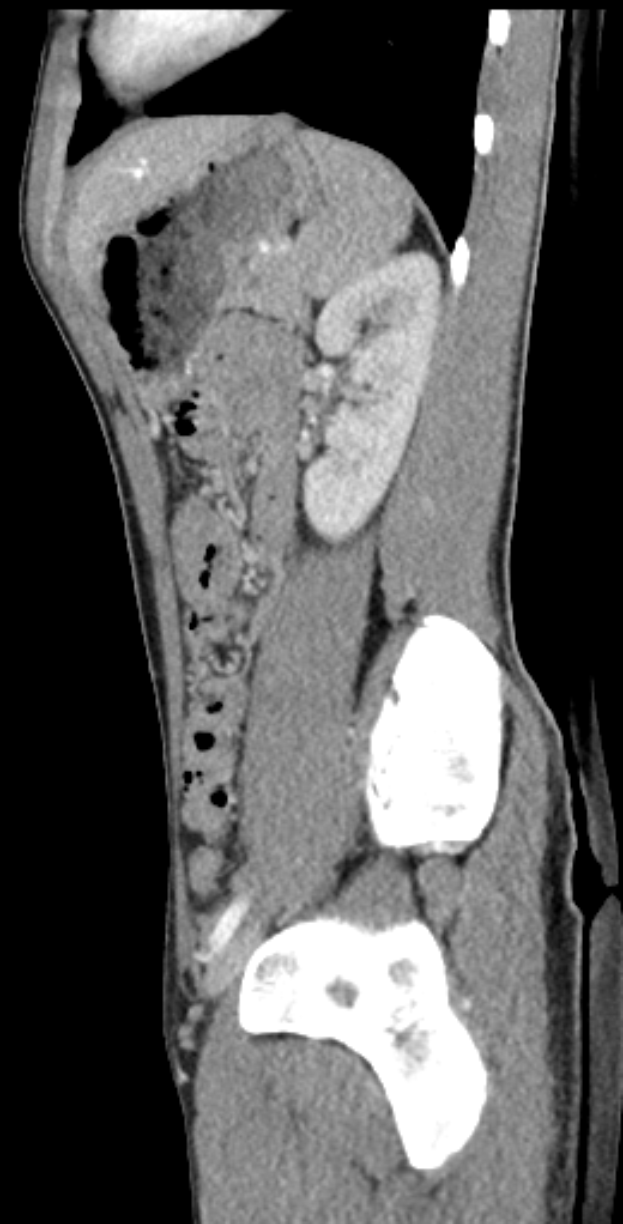

Eine MRT-Aufnahme eines Knies, die einen Bruch in der Mitte zeigt, umgeben von einem dunklen Hintergrund.Johanna Albrecht